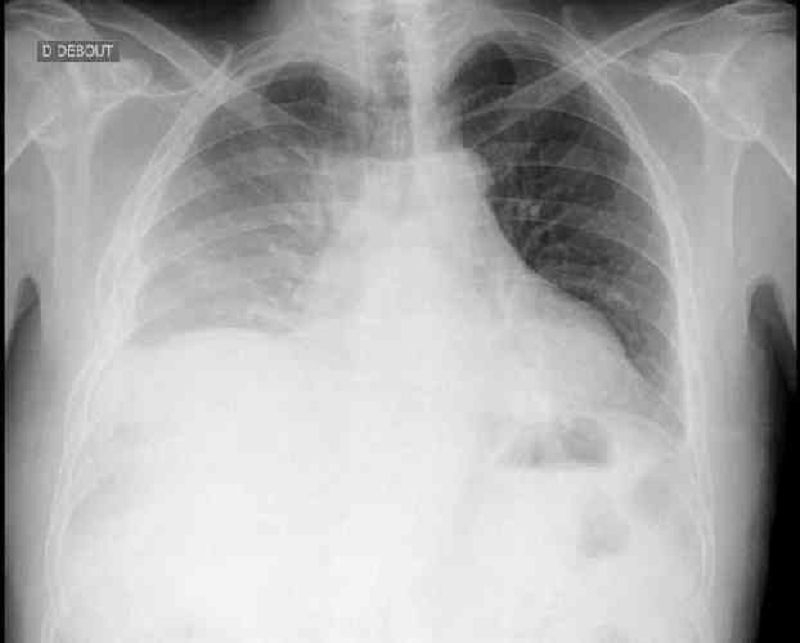

Vous prenez en charge un patient de 61 ans présentant une dengue hémorragique avec epistaxis. Ses constantes sont les suivantes : PA 110/60 mmHg, pouls 95/min, T° 38,6° Sp02 91 %. Il existe une thrombopénie modérée à 87 000/mm3 sur la formule sanguine. Vous demandez une radiographie pulmonaire devant la légère désaturation associé à une polypnée à 28/min. Quel est le diagnostic le plus probable ? @ICONO@

Epanchement pleural

Oedème lésionnel

Pneumopathie bactérienne

Hémorragie intra alvéolaire

Oedème cardiogénique